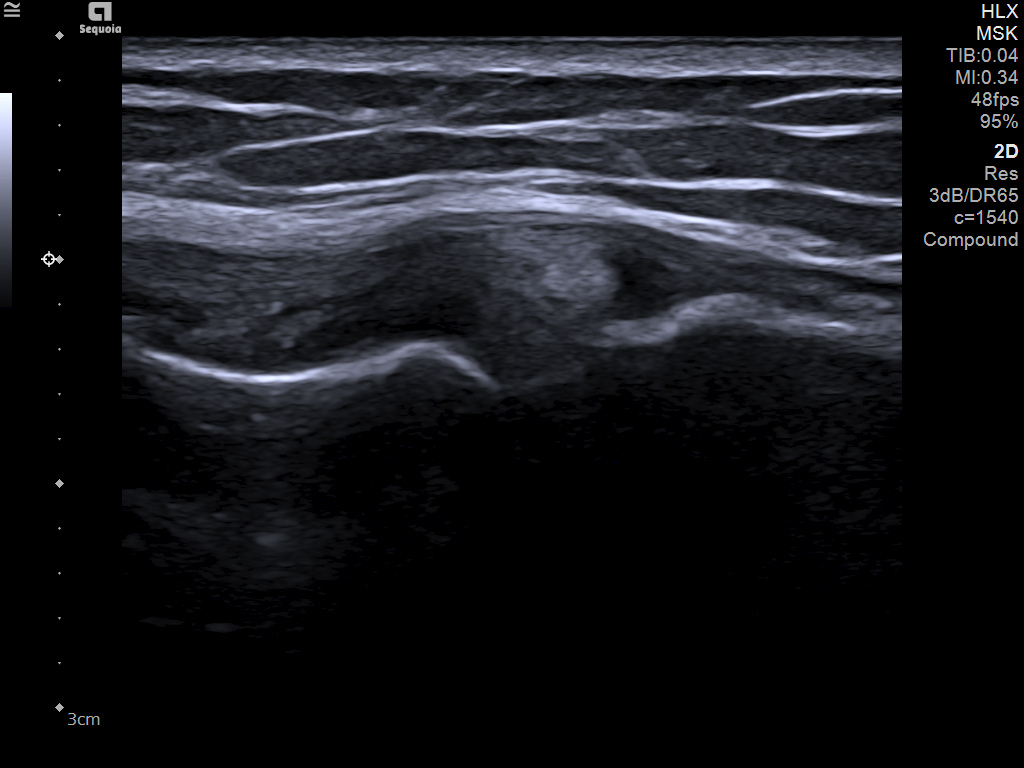

The latest updates on ACUSON Sequoia use the power of groundbreaking AI for abdominal cases, includes advanced breast visualization to deliver new levels of image quality confidence, and tackles the toughest challenges in musculoskeletal imaging, all while saving your team from needless strain and pain.

A clearer, deeper perspective with optimal acoustics for each clinical use case. Expand your assessment with advanced tools that take ultrasound beyond its traditional role.